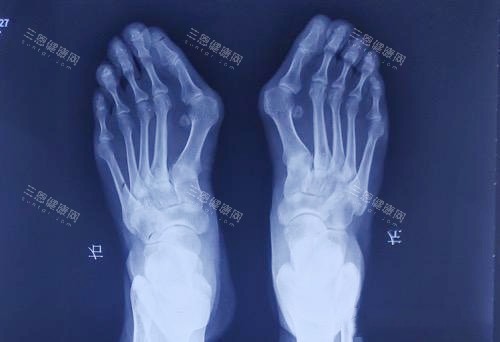

拇外翻手术失败别慌!苏敬达医生修复实例多+小切口技术揭秘~